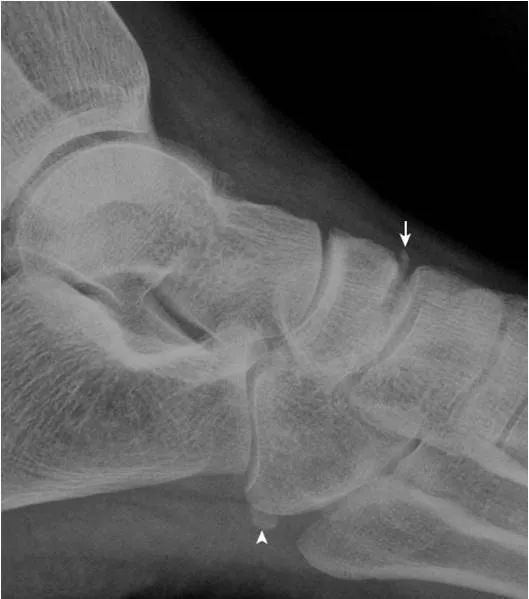

26.距骨鼻区撕脱骨折:

距骨鼻区见小片状骨性密度影,其与距骨对应处见骨质缺损(箭),邻近脂肪间隙密度明显增高,局部肿胀(箭头),提示为撕脱性骨折而非变异。